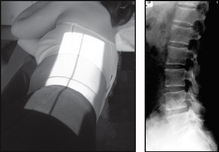

image

Projection: AP

Centring Point: Midline at the level of lower costal margin

Projection: LATERAL

Centring Point: 8–10 cm anterior to the third lumbar spinous process at the level of the lower costal margin